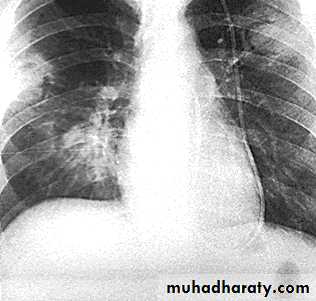

Lymphadenopathy